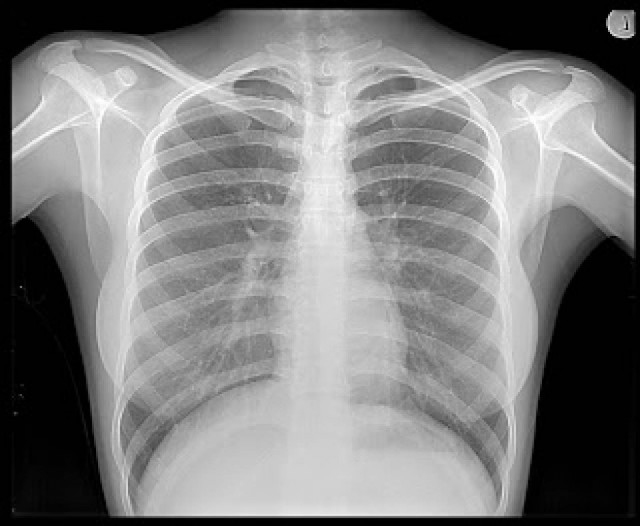

Το 2007 μια 18χρονη νεαρή επισκέφτηκε το Ιατρικό κέντρο του Rush University στο Σικάγο, με παράπονα για πόνους στο στομάχι, εμετούς και ανεξήγητη απώλεια 40 κιλών. Μετά την ακτινογραφία, η οποία έδειξε μια «σκοτεινή μεγάλη μάζα», η νεαρή μπήκε στο χειρουργείο όπου οι γιατροί ανακάλυψαν μια μπάλα από τρίχες βάρους 5 κιλών! Με μήκος μεγαλύτερο από 30 εκατοστά. Εν τέλει, έγινε γνωστό ότι η κοπέλα πάσχει από τριχοφαγία, δηλαδή τρώει τα ίδια τα μαλλιά της. Προφανώς, πολύ...

Ο 57χρονος Daryoush Mazarei βίωνε σοβαρούς πόνους μετά από μια εγχείρηση. Δυο χρόνια μετά την επέμβαση ο ασθενής δεν είχε αναρρώσει ακόμα και όταν διαμαρτυρήθηκε στους γιατρούς, εκείνοι τους σύστησαν ψυχιατρική βοήθεια. Μάλιστα, οι γιατροί του ανέφεραν την ιστορία του Πέτρου με τον Λύκο, παρόλο που η κόρη του ασθενή μπορούσε να δείξει μια εμφανέστατη ακίδα αιχμηρού αντικειμένου που έβγαινε από μέσα του. Τελικά, μετά από ακτινογραφία, οι γιατροί είδαν ένα μεγάλο αντικείμενο στην κοιλιακή χώρα του Mazareiμ η οποία δεν ήταν παρά λαβίδες που ξέχασαν μέσα του οι γιατροί κατά την εγχείρηση.

Η 52χρονη Ολλανδή Margaret Daalman πήγε στο νοσοκομείο με έντονους πόνους στο στομάχι. Η ακτινογραφία έδειξε κάτι που έμοιαζε με ένα τεράστιο, συμπαγές... καλαμάρι. Όταν οι γιατροί άνοιξαν την 52χρονη, έβγαλαν ένα – ένα 78 κουτάλια και πιρούνια!